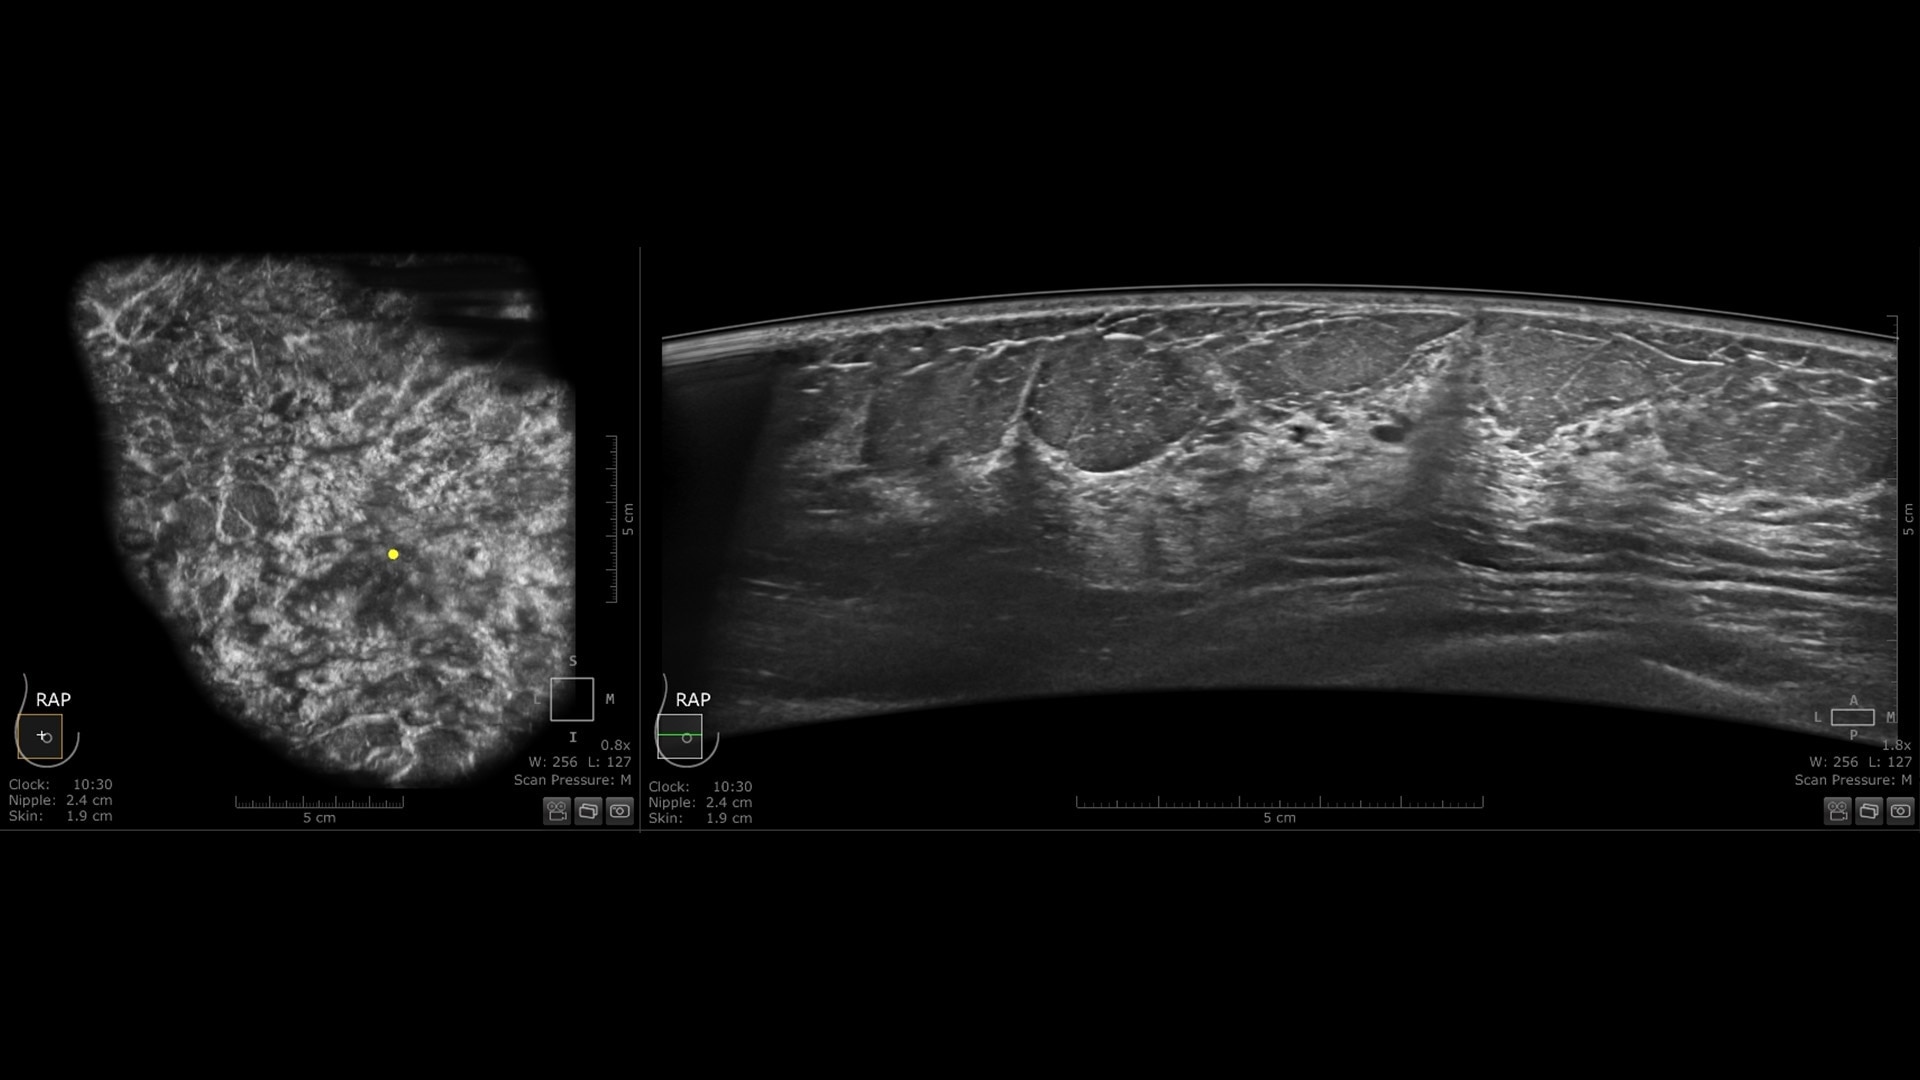

Impactful screening solution

Improve breast cancer detection by 35.7% over mammography alone in dense breasts¹